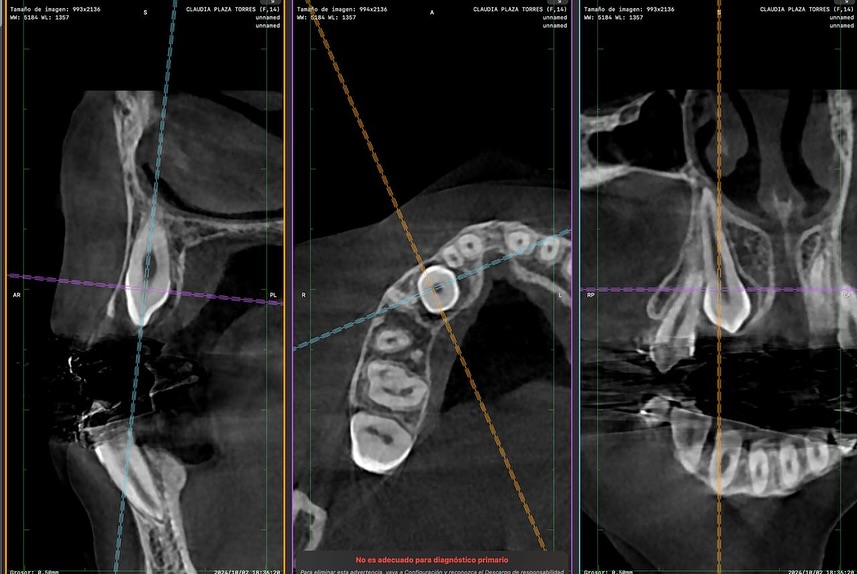

Ofrecemos una estancia clínica en elevación de seno maxilar, diseñada para odontólogos que deseen perfeccionar sus habilidades en implantología avanzada. Durante la formación, el participante tendrá la oportunidad de observar y asistir en procedimientos reales, comprender la planificación